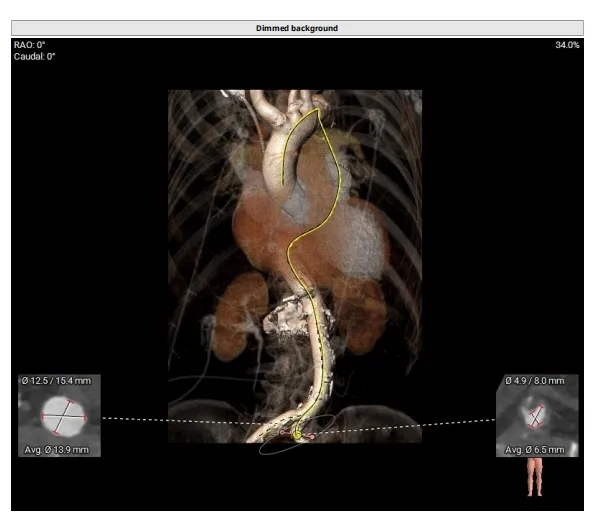

外周入路评估

-

血管轻微迂曲

腹主、弓部可见钙化斑块

血管内径充足

主动脉弓平缓

66°横位心

右侧股动脉主入路,超硬导丝支撑下植入大鞘,左侧辅入路

冠脉风险不高,不进行提前保护,球囊预扩及瓣膜释放过程中评估冠脉灌注情况

建议20mm球囊预扩,患者小心室,小球囊扩张降低循环崩溃风险

使用ScienCrown™全可回收主动脉瓣膜系统植入TF27号瓣膜